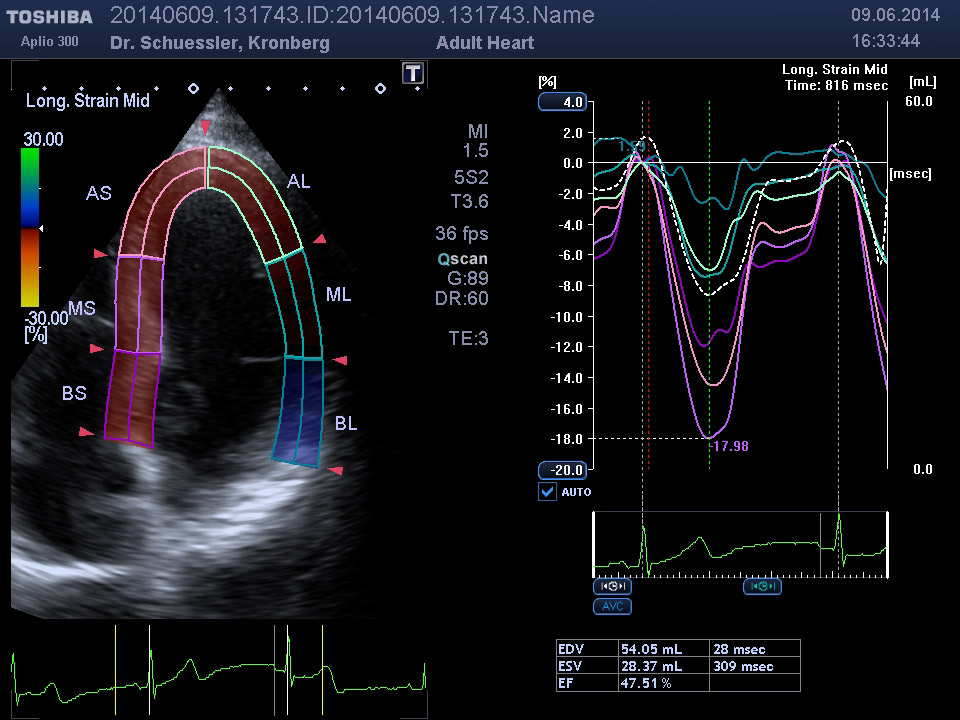

Moderne Auswertungsalgorithmen wie das „Wall Motion Tracking“ erlauben eine isolierte, hochauflösende Darstellung und Analyse der Bewegung und Funktion einzelner Segmente des Herzmuskels.

• Segmentale Bewegungsstörungen des Herzmuskels als Hinweis auf Durchblutungsstörungen